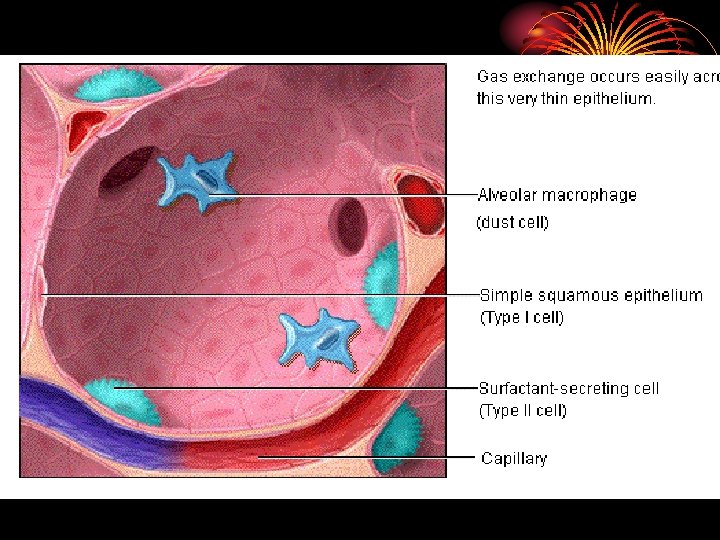

• area from 2. 5 cm 2 (trachea) to 11800 cm 2 in alveoli ? Air velocity. • 300 million alveoli, 70 m 2. • Alveoli lined by type 1 cells ( flat lining ) and type 11 cells ( granular pneumocytes secrete surfuctant ). • Pleura. • Respiratory muscles.

Surfactant • Lipid surface tension lowering agent. • Produced by type II alveolar epithelial cell. • Composed of phospholipids, neutral lipids, proteins and CHO. • Functions: 1. Lower surface tension in alveoli. 2. Helps to prevent pulmonary edema.

Gas transport between lungs and tissues: • Oxygen diffuses out of alveolar gas into the blood stream and CO 2 diffuses from the blood into the alveoli down their partial press. gradients. • Diffusion capacity of the lungs for a given gas is directly proportional to the alveolocapillary membrane (pulm. epithelium, capillary endothelium & their basement membranes) and inversely proportional to its thickness.